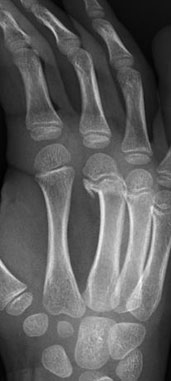

Metacarpal neck fracture

(sometimes labelled a “Boxer’s Fracture” when found in little finger metacarpal)

Left: neck fracture little finger metacarpal Right: neck fracture middle metacarpal

Left: neck fracture little finger metacarpal

Right: neck fracture middle metacarpal